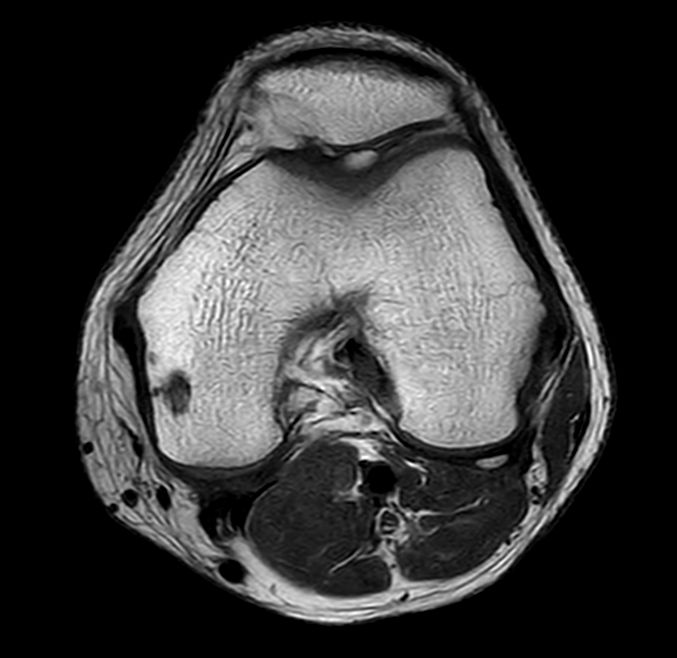

Axial T1w TSE

Axial PDw TSE FatSat